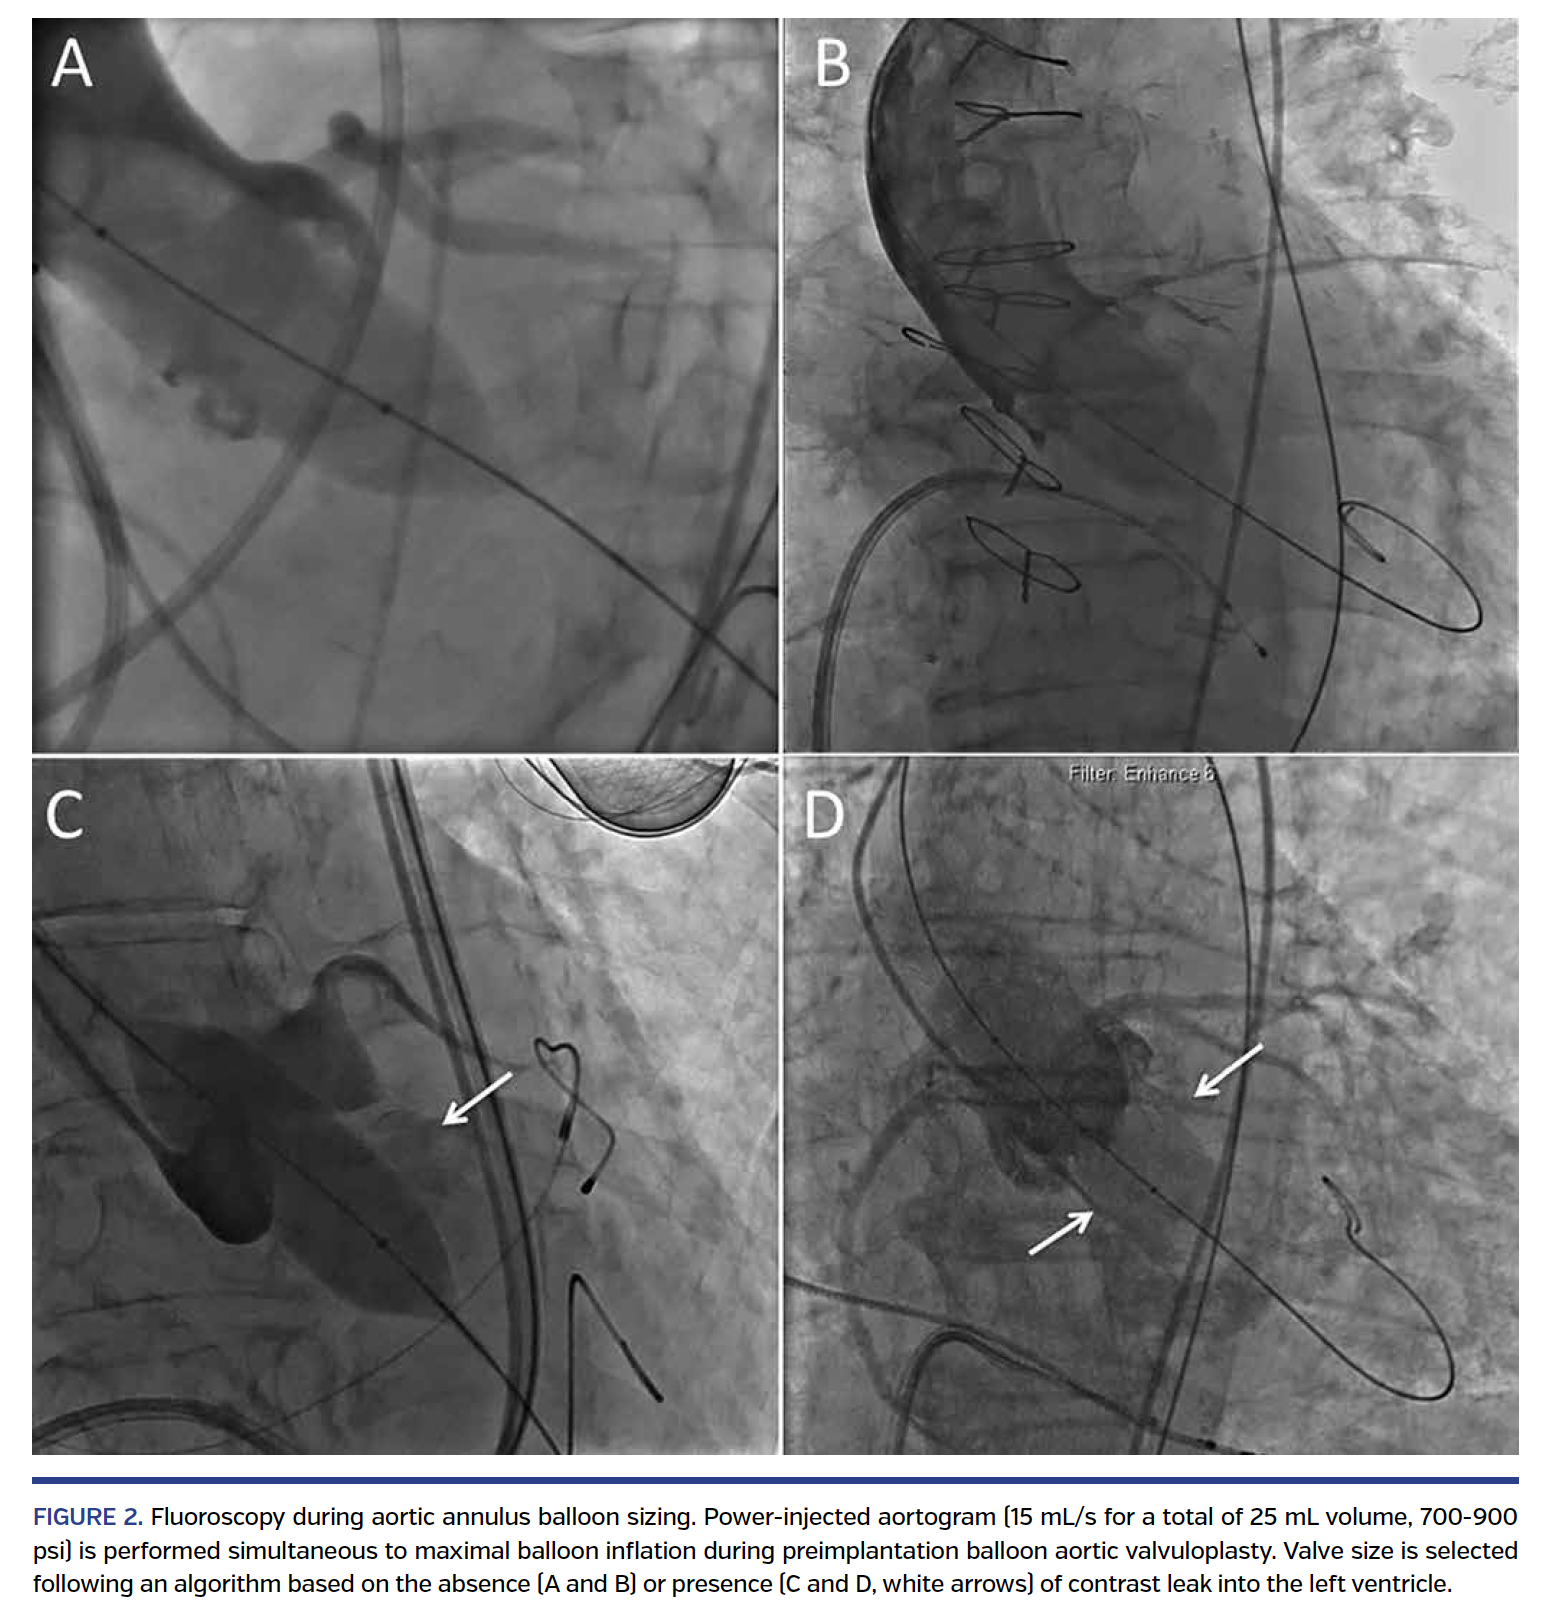

Balloon sizing technique. The balloon sizing technique has been previously described.6-8 In patients with an 18-21 mm annulus size by TTE, a 21-22 mm balloon was used for balloon aortic valvuloplasty (BAV) (Figure 1). A Z-med (Numed) or Edwards Lifesciences balloon was prepared on a sterile table and the volume in the inflation syringe was adjusted so that complete inflation was required to reach final balloon size confirmed by calipers. The balloon was then deflated, inserted retrograde through the aortic valve, and used for BAV during rapid right-ventricular pacing. At full inflation, contrast was power injected into the proximal ascending aorta through a pigtail catheter placed at the level of the sinotubular junction (15 mL/s for a total of 25 mL volume, 900 psi). If contrast was not observed leaking around the balloon, a 23 mm valve was implanted. The presence of contrast leaking around the balloon and into the left ventricle identified the need for a larger valve, and a 26 mm valve was implanted (Figure 2). Similarly, in patients with a 21-24 mm or 24-28 mm annulus, a 24-25 mm or 27-28 mm balloon was used for BAV, respectively. The case was aborted if contrast leak was seen with a 27-28 mm balloon, as the largest available Sapien XT valve is 29 mm. We favor the use of a 2 mm difference between balloon and valve size (consistent with ≥10% oversizing by area).